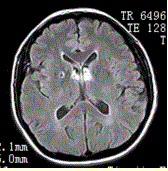

问题 男性,55岁。临床偶尔头晕,无高血压,糖尿病病史。MRI显示如下图。 可能的诊断是

选项 A.血管周围间隙 B.腔隙性脑梗死 C.神经上皮囊肿 D.脑囊虫 E.囊性肿瘤

答案 A